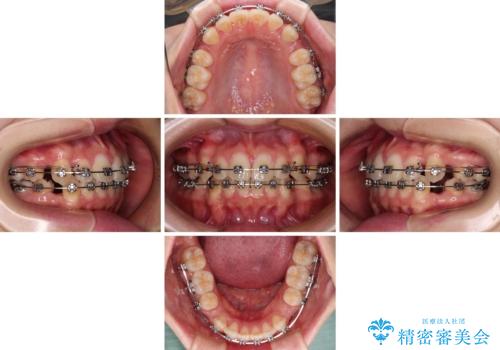

- メタルブラケット

上下ともに歯列が前方に突出していたため、上下左右の第一小臼歯4本を抜去し、ワイヤー装置による矯正治療を行うこととしました。

上下左右4本抜歯する場合には、通常2年から2年半ほどの期間を要しますが、舌のトレーニングをしっかりと行っていただいたことで、1年9ヶ月で終了することができました。